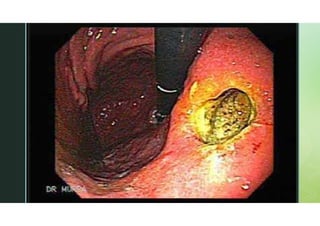

Endoscopia

IMAGEM

O QUE É ENDOSCOPIA E PARA

QUE SERVE?

 A endoscopia é um exame capaz de analisar a mucosa

do esôfago, estômago e duodeno (primeira parte do

intestino delgado).

 É feita através de um tubo flexível (conhecido por

endoscópio) que possui um chip responsável por

capturar as imagens do sistema digestivo através de

uma câmera.